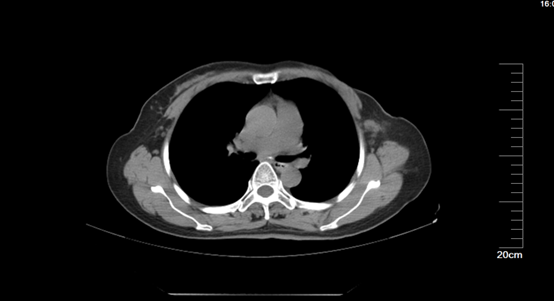

2、单孔腔镜乳腺癌保留乳头乳晕皮下腺体切除术+腋窝前哨淋巴结探查术

微信图片_20221202184931.png

手术病例为48岁女性,仅有一处手术切口,隐蔽于腋窝皮肤皱襞处,长度约2.5cm,先行腋窝前哨淋巴结探查术后行乳腺癌保留乳头乳晕皮下腺体切除术。病理结果为乳腺癌,前哨淋巴结未见转移。

微信图片_20221202184809.jpg